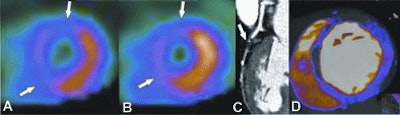

| Fifty-eight-year-old woman with recurring chest pain. Extensive, fixed perfusion defect is observed at stress (A) and rest (B) SPECT myocardial perfusion imaging. Contrast-enhanced retrospective electrocardiogram-gated DECT study: Coronary CTA reconstruction displayed as curved multiplanar reformat (C) shows total thrombotic occlusion of the distal left anterior descending artery to the first diagonal branch (arrow). Short-axis view (C) shows corresponding anteroseptal contrast defect (arrows) in good correlation with fixed perfusion defect at SPECT. |